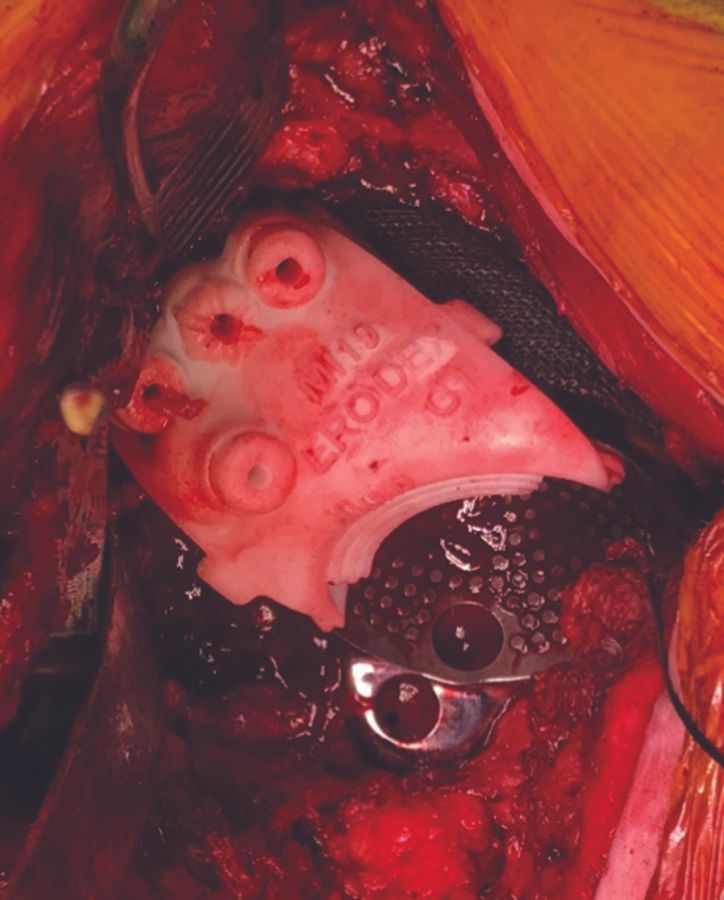

According to the preoperative plan on the 3-D model primary fixation is achieved with multiple screws in the ilium, ischium, and pubic bone using the drill guides (figure 7).

Screw length is also predetermined and can be double checked with the surgical guide. In case of a pelvic dissociation we start the fixation inferiorly in order to prevent pushing the ischium and pubic away during the insertion of the flange and screws. After inferior fixation the implant is fixed to the ilium together with the reduction of the dissociation (figure 8).

Finally, a dual mobility cup is cemented into the implant and reduction of the femoral head is performed (figure 9). In case of severe abductor deficiency, we prefer the use of a constrained cup.